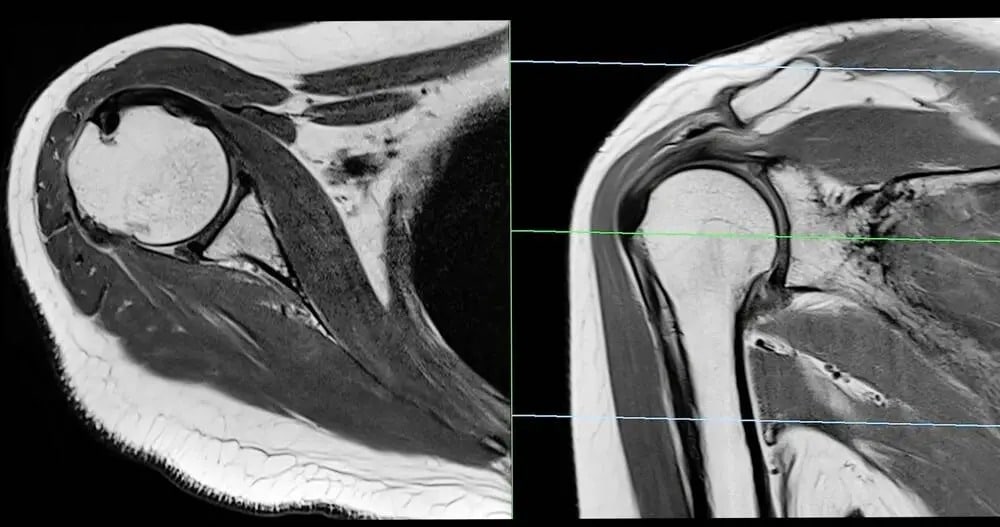

MRI relies on powerful magnetic fields and radio waves to generate images of the body’s interior. This approach makes it particularly effective for soft tissue imaging since it captures the contrast between different types of tissues. With the ability to highlight fine details, MRI scans can detect tears, swelling, or abnormalities within soft tissues.

The process involves placing the patient within a cylinder-shaped scanner that takes cross-sectional images of the area under observation. These images allow physicians to pinpoint the nature and location of an injury more accurately than other imaging methods. This accuracy is especially relevant in sports-related injuries.

Soft tissue injuries span a range of conditions, many of which benefit from the clarity provided by MRI imaging. Ligament injuries, such as ACL or MCL tears in the knee, are frequently assessed using this technology. Tendon conditions are often diagnosed through MRI scans. MRI is also used for more complex conditions affecting soft tissues, including tumors or cysts. By offering clear images of soft tissue masses, this helps in detection and evaluation, guiding physicians in determining whether further treatment is necessary. Detailed imaging is valuable not only for identifying initial issues but also for monitoring recovery, as it allows tracking of tissue repair over time.

MRI also supports detailed, multi-plane views of the affected area. These comprehensive perspectives give medical professionals a complete understanding of the injury. This level of detail reduces the margin of error in diagnosing soft tissue injuries, ultimately aiding in the selection of the most appropriate therapy or intervention.